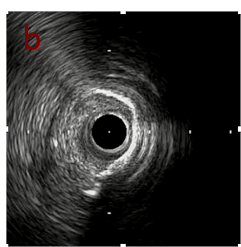

IVUS after OAS high speed 3回

IVUS imaging after high speed 3回

a,b,cはさらに石灰化に食い込み、石灰化量は減少。

それに伴いdではbiasがさらにtentingのIVUS所見にへんかしhigh injury riskと思われた。

引き続き造影で確認してpinpointで引きのOAS high speedを3回さらに追加のためcでIVUSマーキングを行い、その点より引きで赤線のpinpoint OAS high speedを行い、dに関してはinjury回避のためにOASを当てない方針とした。